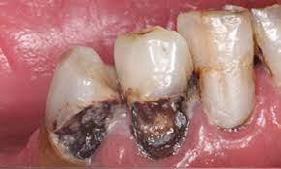

Caso 4

Se presenta un paciente de 43 años de edad con deficiente higiene dental y con gingivitis en el sextante anterior inferior del canino 33 al canino 43 presencia de bioplaca con puntuación de 3 mala y sarro subgingival, (Figura 11). Por la existente acumulación del sarro se recomendó realizar la profilaxis con el cavitron, el cual es un instrumento ultrasónico que trabaja con presión de agua y que facilita el detartraje (Figura 12).